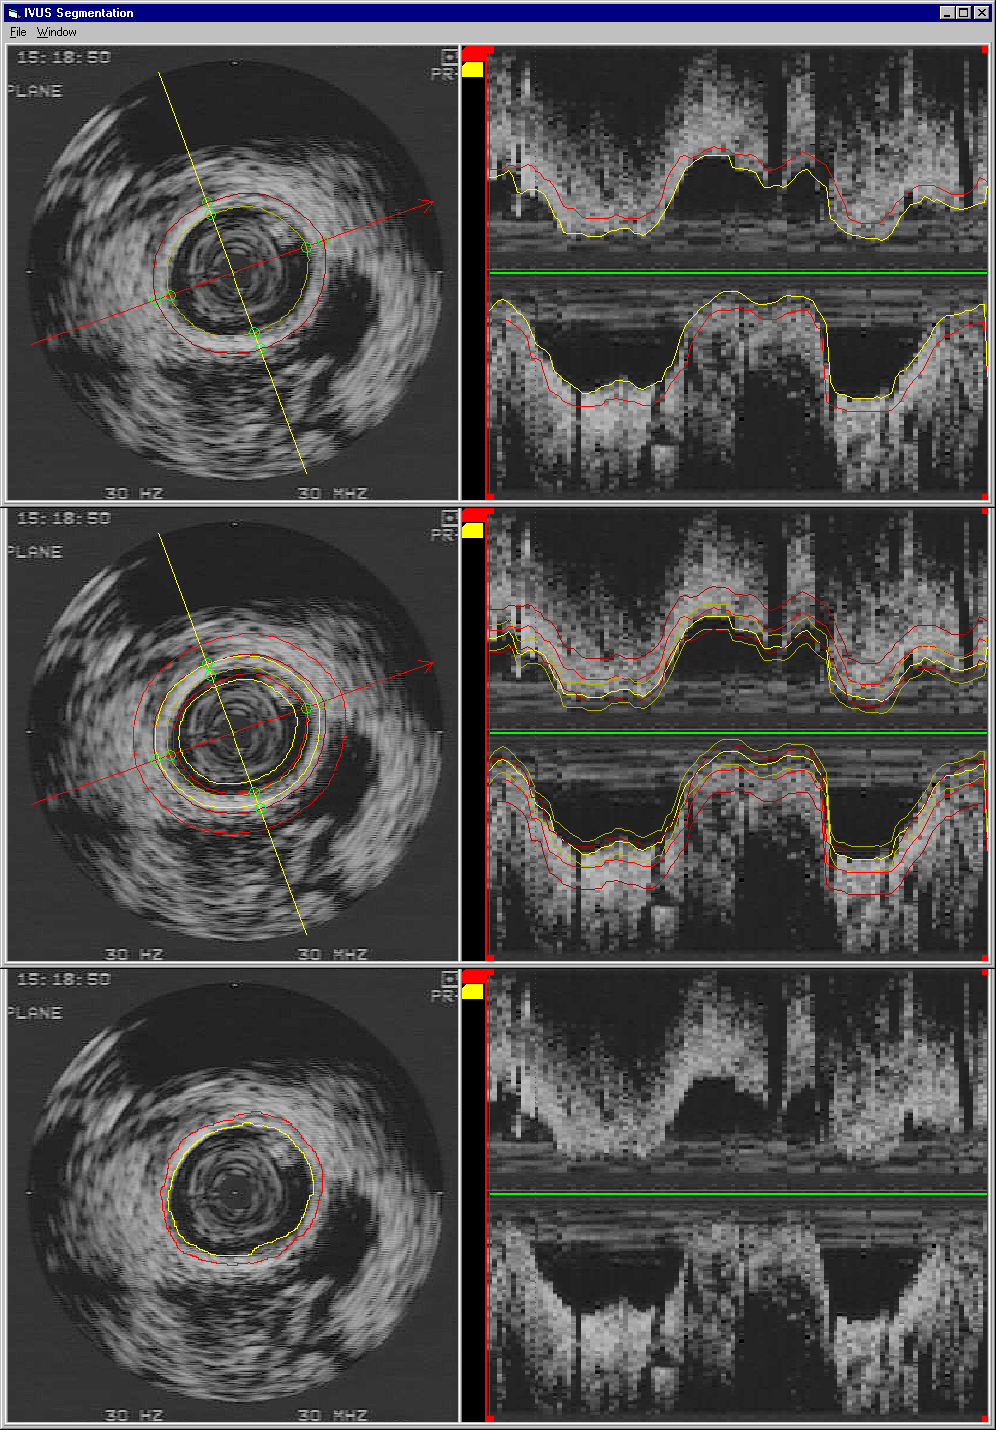

Semi-Automated Segmentation of the IVUS Data